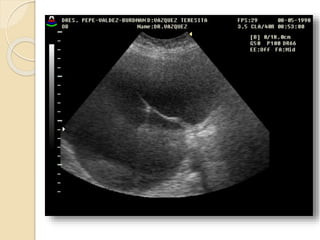

Quistes Endometrósicos:

Clínicamente se manifiesta por dismenorrea,

dispareunia e infertilidad.

La lesion mas detectable por la imágenes esta

constituida por los quistes endometrosicós

(endometriomas) que se forman a partir de los

implantes ováricos configurando los quistes

“achocolatados”.

Se observan quistes de paredes relativamente

gruesas e irregulares con débiles ecos en su

interior debido al contenido hemático.